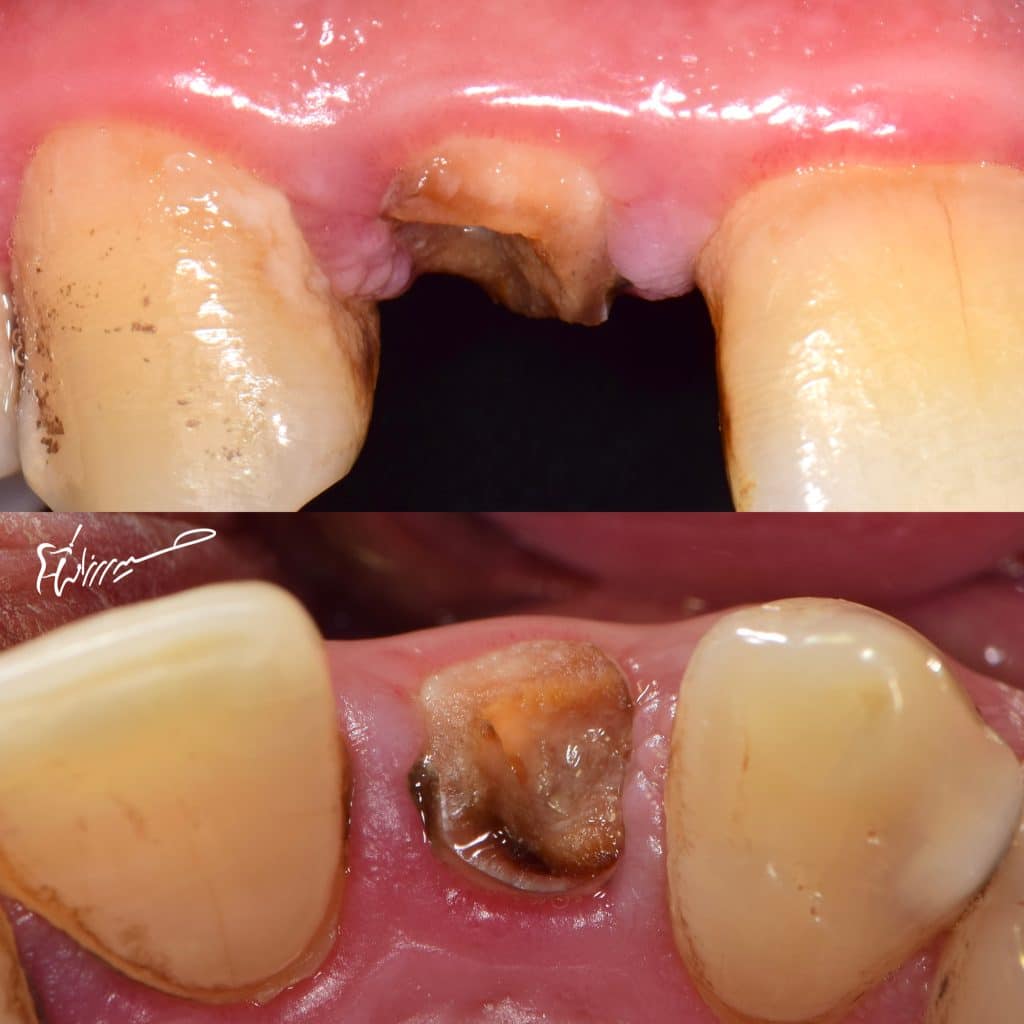

The first comment when you see cases like this is : bad prognosis! , it will fall soon ! Where is the fiber post ?!

Let’s us talk about the materials used in this case and the techniques ..